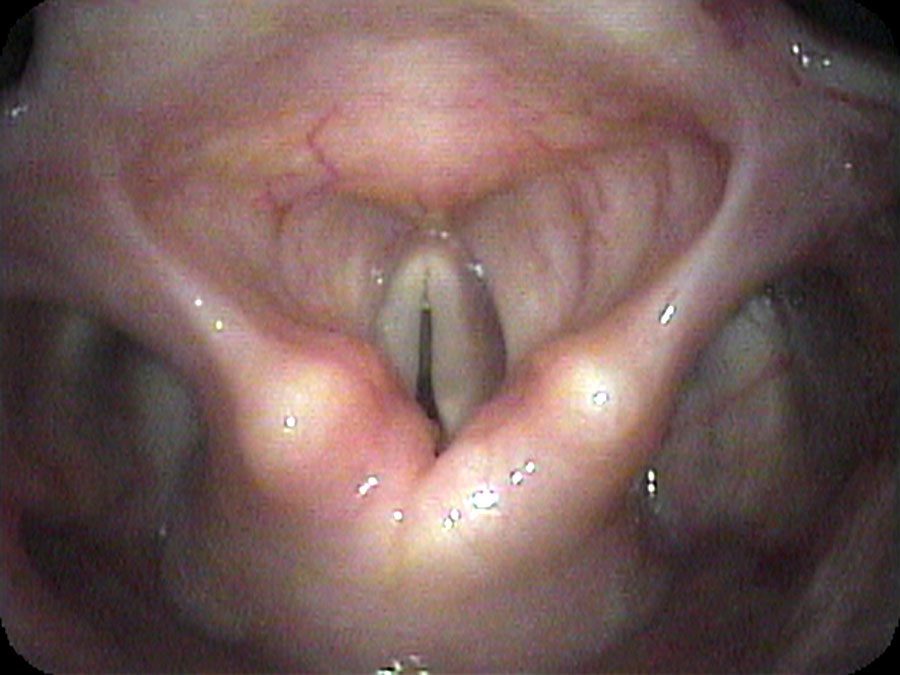

I drip some numbing medication onto her vocal cords and pass the endoscope under the arytenoids at the back of the larynx — looking at the area where the endotracheal tube would have been sitting for 10 days. I find a band of scar tissue just beneath the vocal cords, holding the vocal cords together. At most, she can open her vocal cords about 2 millimeters because of this scar band.

- A scar band (posterior glottic stenosis) from prolonged intubation is mechanically distinct from vocal cord paralysis — but both produce similar-appearing immobility on a standard endoscopic overview.

- Passing the endoscope beneath the arytenoids and very close to the posterior commissure is the only way to directly visualize a scar band in this location.